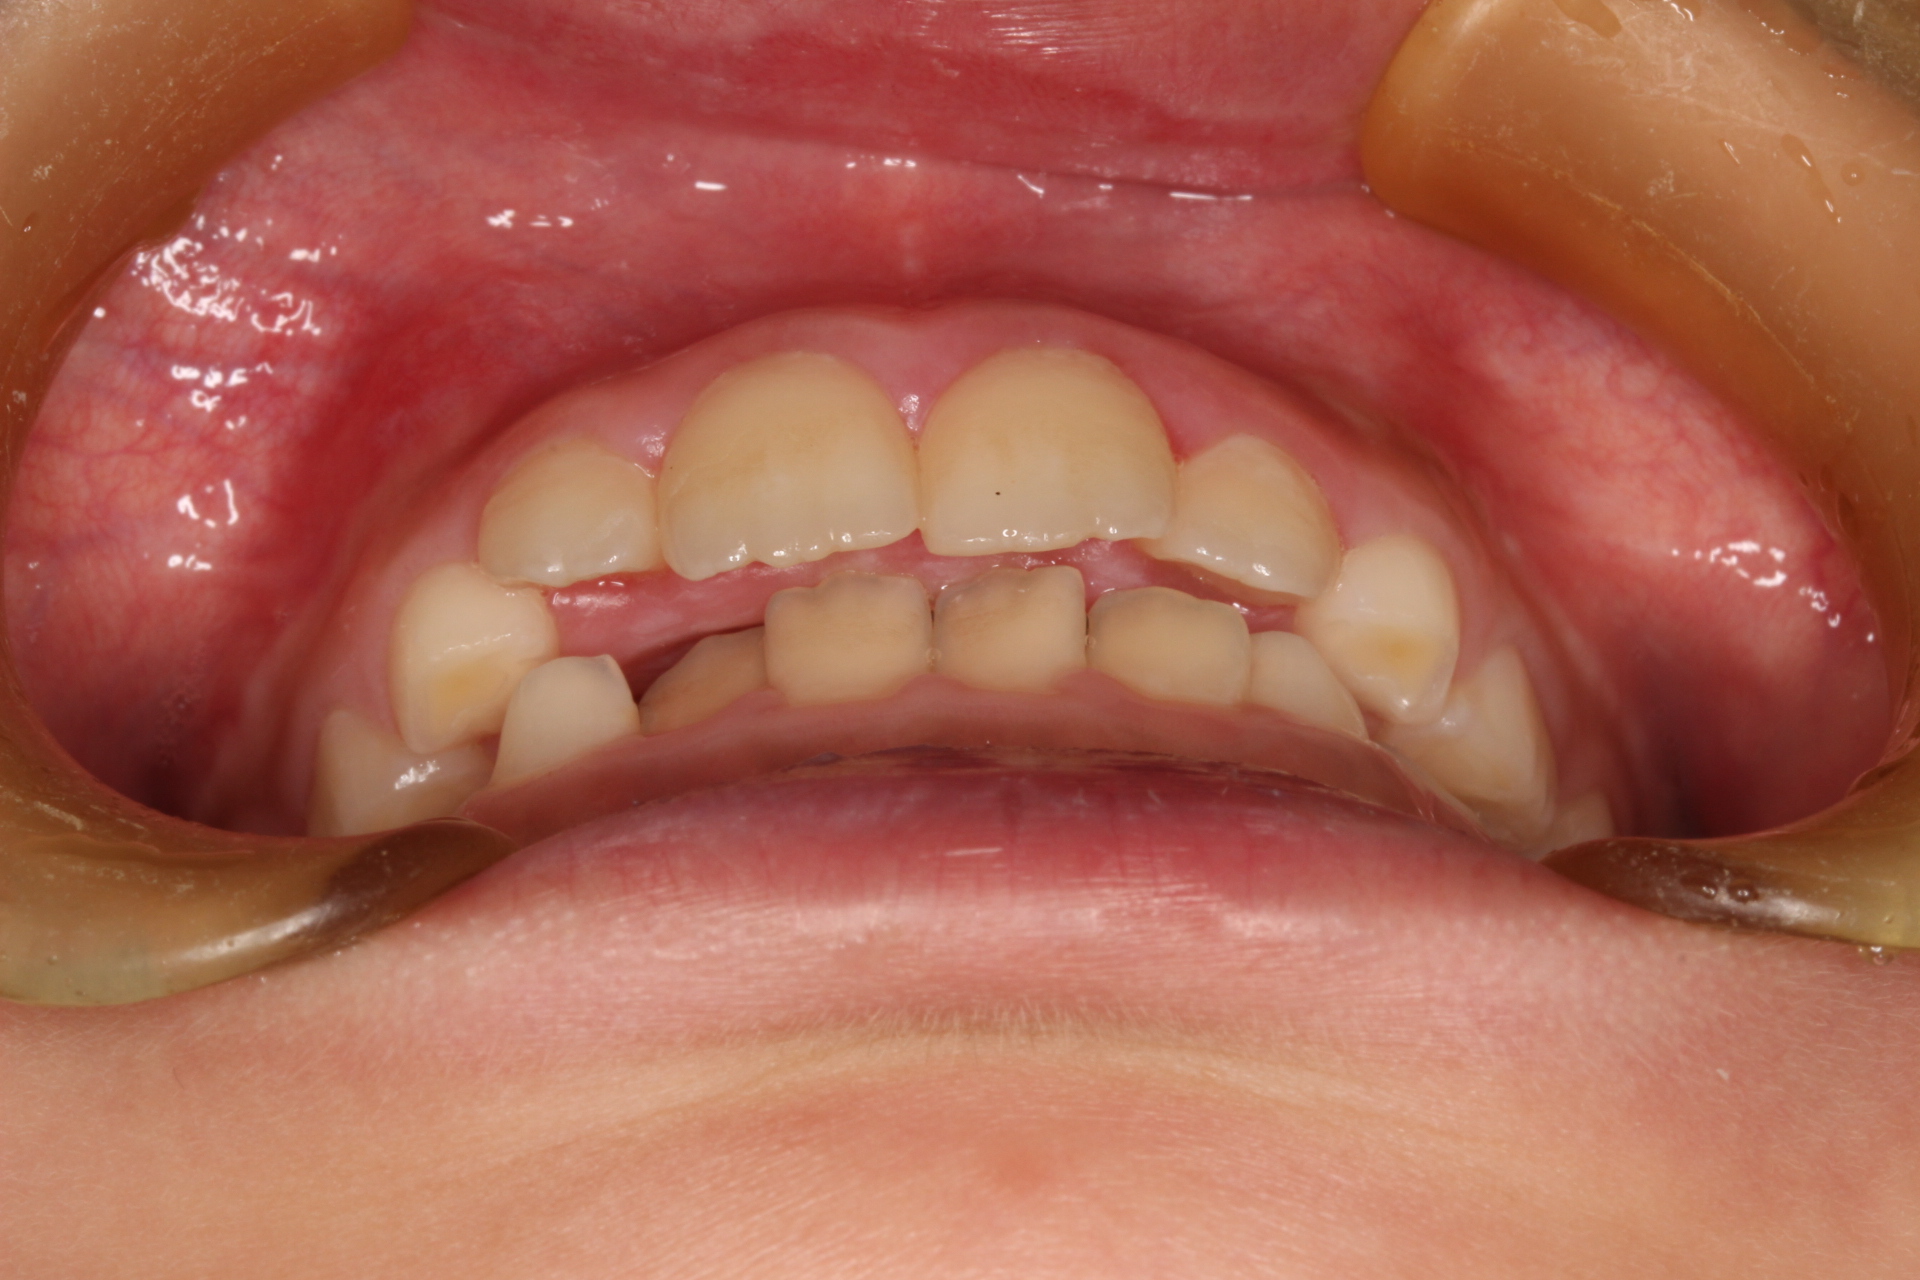

矯正術前:正面

矯正術後:正面